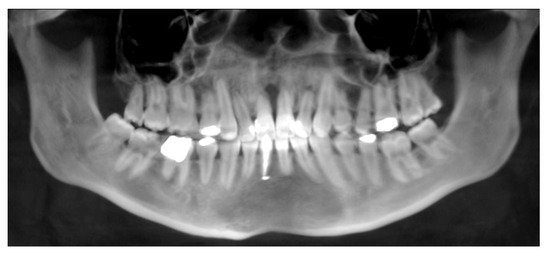

| No possibility of distraction—1 case | Maxillary incisor root resorption—2 cases |

| Palatal mucosal necrosis—2 cases | Bone loss/lack of adhesion in the distraction gap—5 cases |

| Perforation of the maxillary alveolar process caused by the distractor—1 case | Maxillary incisor necrosis—2 cases |

| Asymmetric distraction—5 cases | |